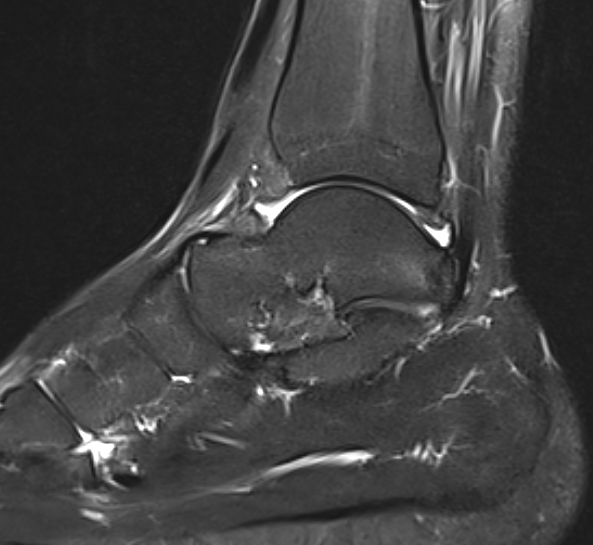

MRI

Findings

- synovitis over posterolateral process talus

- fluid in sheath about FHL

- edema around os trigonum

- edema posterior tibia bone

- thickened posterior capsule

Os trigonum FHL tenosynovitis with posterior ankle joint soft tissue

Stieda's process with ankle joint effusion